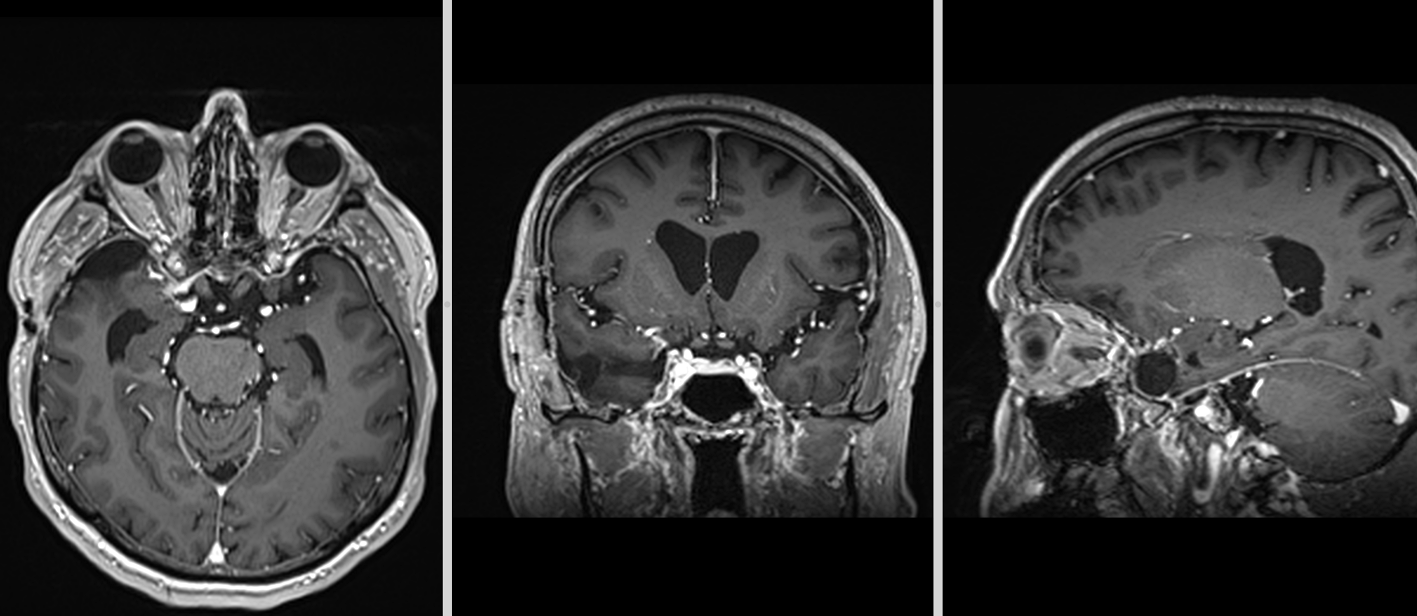

Evoluția postoperatorie a fost favorabilă, fără complicații neurologice. Pacientul a beneficiat de monitorizare clinică și imagistică periodică, conform protocoalelor moderne de urmărire pentru tumorile cerebrale benigne.

RMN postoperator la 6 luni